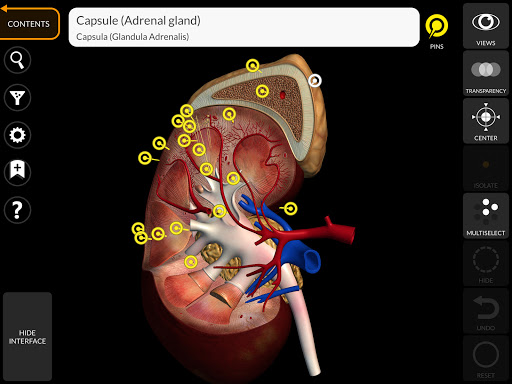

"Anatomy 3D Atlas" дозволяє легко та інтерактивно вивчати анатомію людини.

Завдяки простому та інтуїтивно зрозумілому інтерфейсу можна спостерігати кожну анатомічну структуру під будь-яким кутом.

Анатомічні 3D-моделі особливо деталізовані та мають текстури з роздільною здатністю до 4k.

• Ендокринна система

• Можливість приховування або ізоляції однієї чи кількох вибраних моделей

• Вибравши модель або шпильку, з’явиться відповідний анатомічний термін

• Анатомічні терміни можуть відображатися двома мовами одночасно.